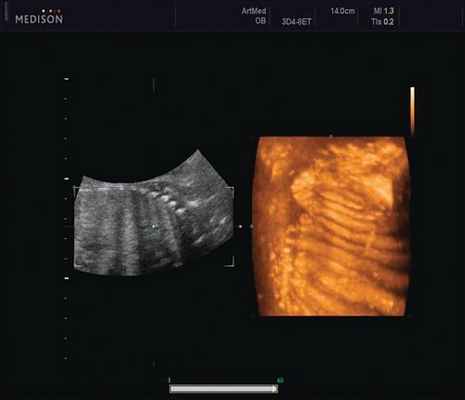

Пациентка К., 26 лет, обратилась в клинику в 23 нед беременности. Беременность первая. Исследование проводилось на аппарате Accuvix-XQ (Samsung Medison) с использованием режима поверхностной объемной реконструкции 3D/4D. Показатели фетометрии полностью соответствовали сроку беременности. В процессе сканирования позвоночника во фронтальной и сагиттальной плоскостях выявлена угловая деформация позвоночника в грудном отделе, протяженностью около трех позвонков. В поперечной плоскости сканирования нарушения структур и целостности тканей не было обнаружено. В режиме 3D/4D реконструкции было выявлено асимметричное расхождение ребер правой и левой стороны грудной клетки (рис. 4).

Рис. 4. Эхографическая картина асимметрии ребер в режиме 3D реконструкции.

Ребра левой стороны были сближены, межреберные промежутки уменьшены по сравнению с противоположной стороной (рис. 5, 6). Другой патологии у плода не было выявлено. Заподозрен врожденный сколиоз, основой которого является наличие боковых полупозвонков (hemivertebrae) или боковых клиновидных позвонков. В 26 нед ультразвуковая картина сохранялась. При проведении трехмерной эхографии получено отчетливое изображение асимметрии реберных дуг и сколиотическая деформация позвоночника.

Рис. 5. Асимметрия межреберных промежутков в режиме 3D реконструкции.

Рис. 6. Асимметрия межреберных промежутков в режиме 3D реконструкции.